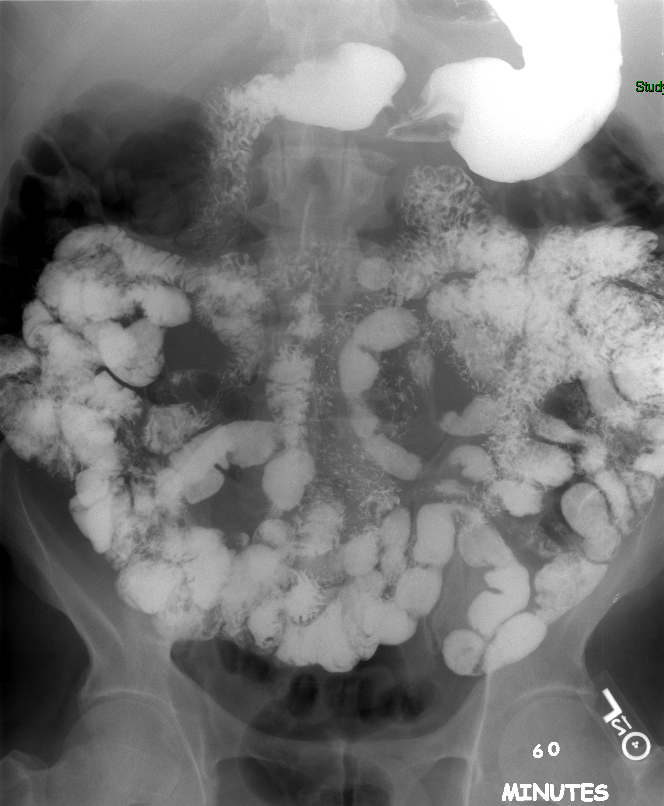

- The technologist will obtain radiographs at 30, 45, and 60 minutes after the initial administration of barium. If the column of contrast material has not reached the large bowel on the 60 minute film, the technologist will obtain images every 30 minutes until contrast can been seen in the cecum

(key image 3)

(key image 4)

(key image 5).